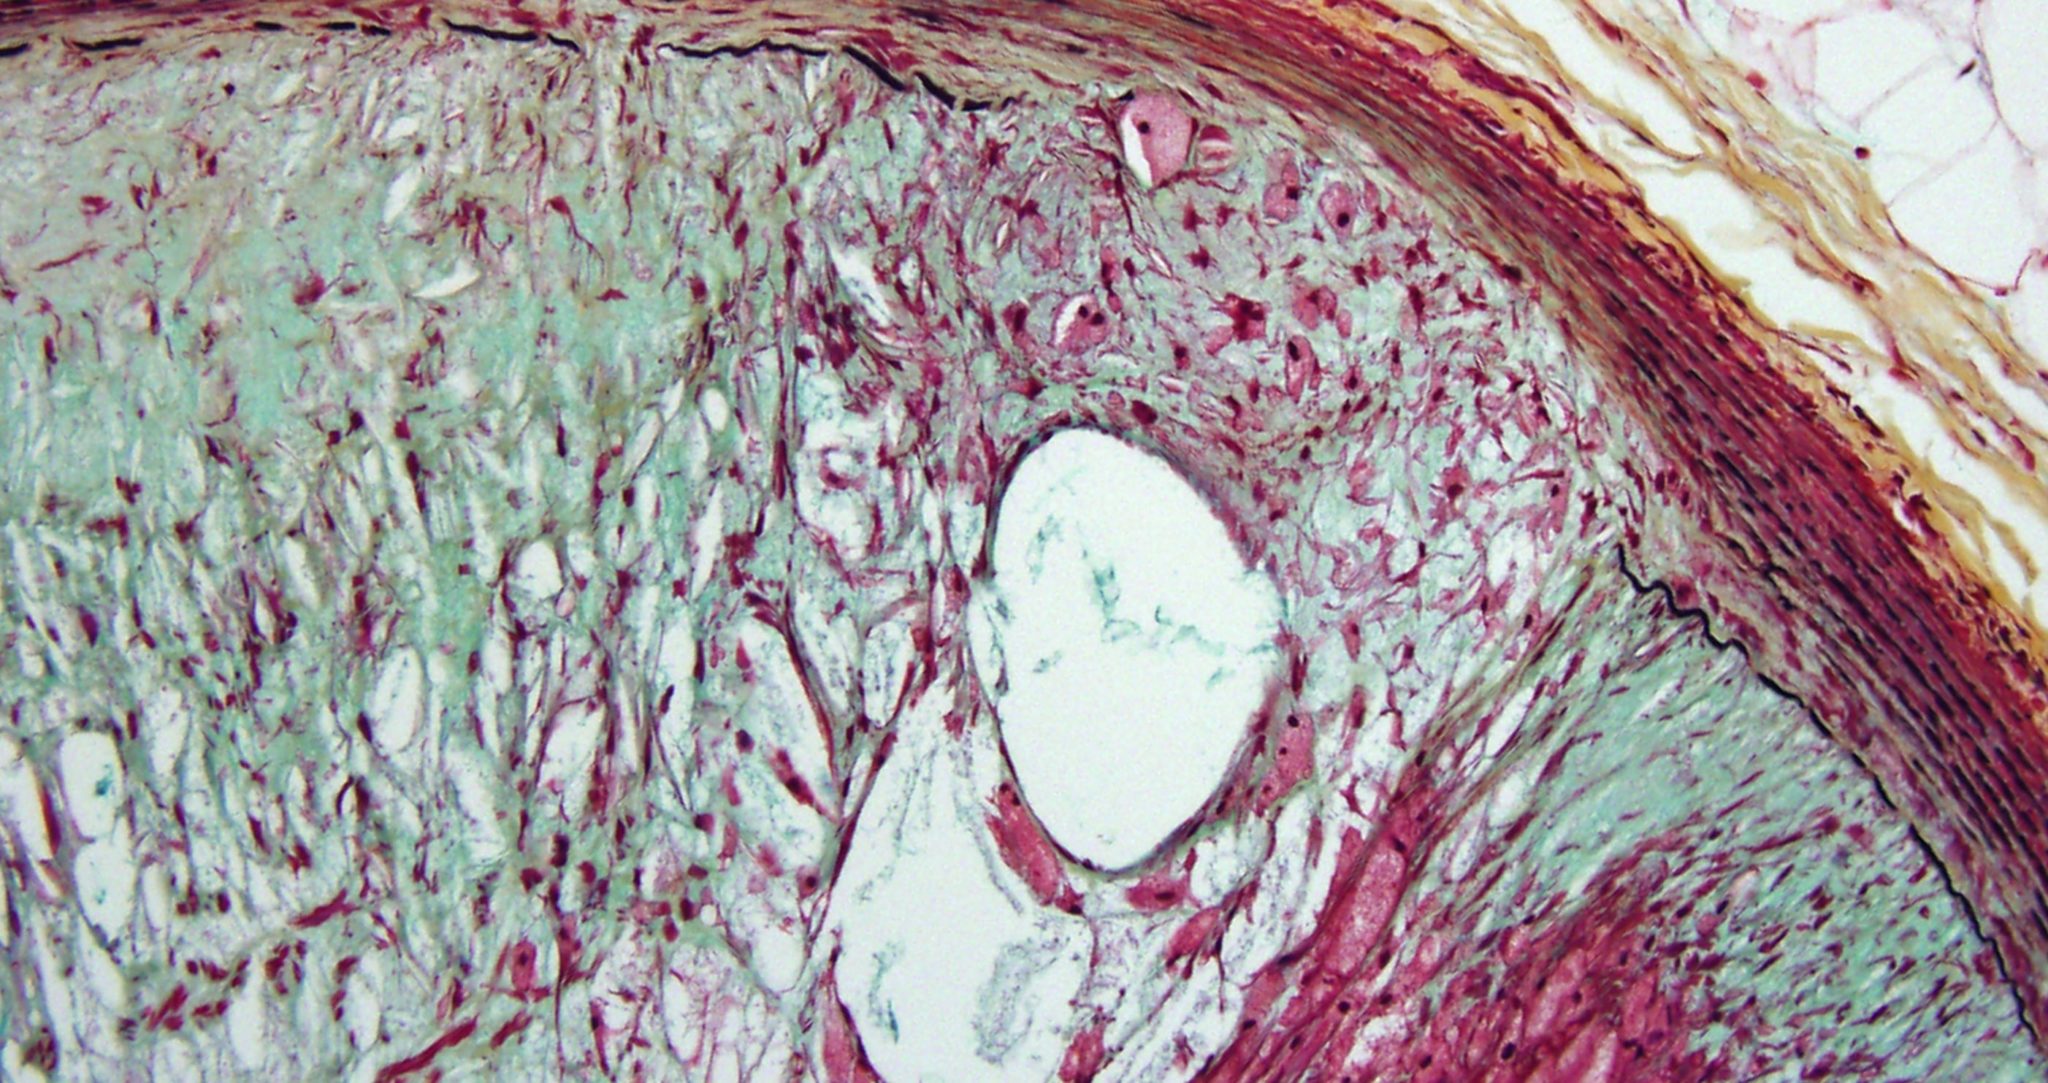

As a vital part of the Institute’s overall cardiovascular research team, THI’s cardiovascular pathologists work to provide researchers with critical information they need to progress their studies forward.